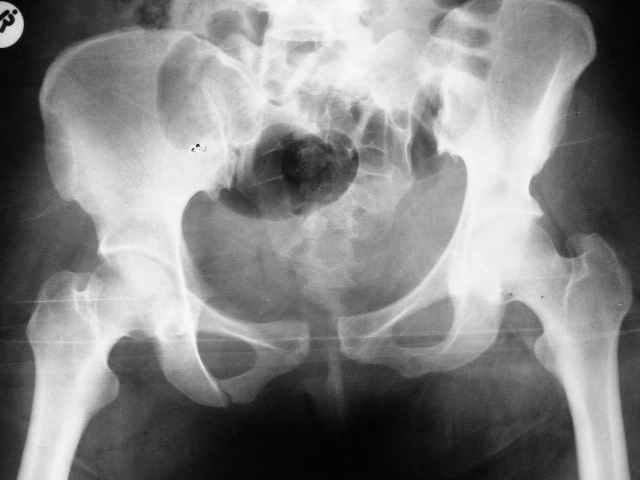

SI joint injury

Больная 28 лет от роду попала в ДТП 12.12.04Что бы вы предложили.заранее признателен,Евгений И Чекашкин

У нас бы аппаратом все вправили, потом ввели закрыто винты через крестцово-подвздошное, а сперелди - пластину.

Сегодня утром прооперировал: на симфиз пластину на 4 винтах и два 6.5 мм винта с неполной резьбой на левое крестцово подвздошное сочленение. (пришлось открыть - девушка весьма внушительной комплекции и пропальпировать крыло и ости не представлялось возможным, спасительного в таких случаях набора канюлированных винтов в госпитале нет). Проконтролировал качество репозиции ЭОПом - остался доволен.

Женя, привет! Поностью согласен с Джолдасом, только дал бы тягу за правую ногу по длине с гтперкоррекцией, а потмо наложил аппарат с 2-мя стержнями с каждой стороны в надацетабулярной зоне под острым углом друг к другу. Если же совсем упростить и сделать конфетку из ... то можно больног туго запеленать через крылья и вертелы и зашить - постельгый режим до 1,5 - 2 мес. А еще раньше мы таких лечили в гамаке. А сейчас, если ты помнишь наши разговоры о тазе - оперируем в cрочном порядке после подготовки из надлобкового доступа большими пластинами на 10 - 12 отв., которые позволяют после домоделирования восстановить конфигурацию тазового кольца и устранить смещение и спереди и сзади. Поднимать можно на следующий день без опоры на левую ногу на стороне порвежденного КПС, если хочешь м опорой - то надо еще 2 винта провести через КПС закрыто. ЛАФ.

В представленном ранее случае вертикальное смещение левой половины таза было минимальным и после плэйтин лонного сочленения незначительное вертикальное и заднее смещение полутаза было устранено, поэтому задняя фиксация и не составила проблемы. Но это свежий случай, оперированный через неделю, отсроченная фиксация, видимо, не будет столь простой. У меня спонтанно сложился подход к стабилизации переломов таза с нарушением тазового кольца: сначала передний отдел (пластина), потом задний - 2 винта. Имея ввиду свежие случаи, у вас такая же последовательность или наоборот. Про фиксацию реконструктивной пластиной на 10-12 винтах в данном случае даже и не подумал (обещали привести тазовый набор, но как- то не очень уверенно- праздники и у основной массы рождественское настроение), к тому же слишком обширная диссекция тканей, когда можно было обойтись меньшей кровью, да и передняя колонна вроде бы не задействована... Помимо ранней активизации и эластического бинтования ног или чулков как вы проводите профилактику тромбоэмболий, как рано после травмы назначаете антикоагулянты.